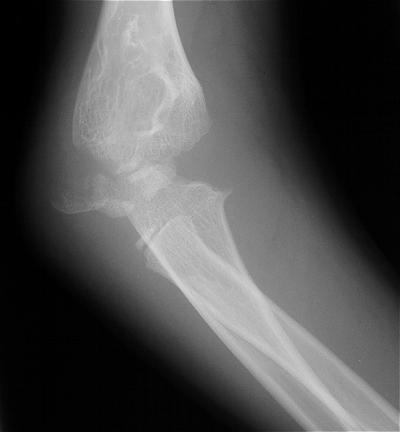

Plain films show humeral osteophytes and posttraumatic changes of the capitellum and radial head.

Postoperatively, pain is improved, although some clicking persists. Range of motion is marginally improved. Radial head excision remains an option if he has painful problems later.